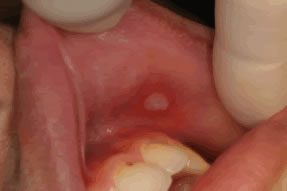

もっとも多く見られる口内炎アフタ性口内炎とは?八潮の歯医者 - LeaLea歯科・矯正歯科クリニック。

アフタ性口内炎浅草 田中歯科医院。

画像・症例写真あり アフタ性口内炎セルフチェックのポイント・治療法歯・口の病気All About。